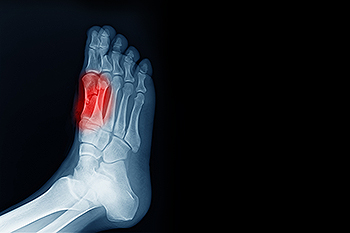

To conduct a diagnosis, the podiatrist will examine the ball of the foot and big toe. They will look for any outliers and check the movement of the toe. X-rays will be taken to rule out any other conditions and ensure that it is sesamoiditis.

The group of bones that are under the bottom of the big toe include the sesamoid bones. They protect specific tendons in the foot, and absorb most of the weight on the inside of the foot. The condition that is known as sesamoiditis occurs when the sesamoid bones become inflamed. They can become injured as a result of enduring a stress fracture, or from an injury that comes from repetitive motion consisting of dancing. Many patients need to have a proper diagnosis performed, which includes having an X-ray taken that can rule out a fracture. Correct treatment techniques can possibly reduce painful symptoms, in addition to protecting the foot from further injury. These can consist of wearing orthotic insoles, taking anti-inflammatory medication, or possible surgery. If you feel you have injured your sesamoid bones, it is strongly urged that you confer with a podiatrist who can help you to manage this condition, in addition to offering you correct treatment solutions.